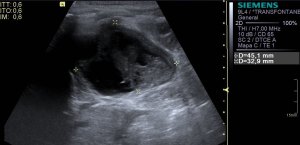

La imagen 3 y 4, como son tan nítidas, puedes ver como el quiste de Baker no es un quiste de Baker simple, la pared es grosera, tiene septos y ecoestrusturas que hacen pensar que el quiste ha podido sufrir algún sangrado. Hay que descartar la formación de lesiones sólidas o polos sólido en los quistes (usando doppler), por norma general, en todos aquellos quistes que estudiemos, en otras localizaciones, por ejemplo, en la mama, en el abdomen, etc.